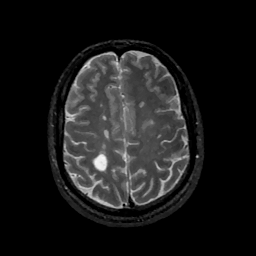

MR Study #11, May 5, 1991 -- Slice #37

[Home][Help][Clinical][Tour 1][Tour 2] Slice 37